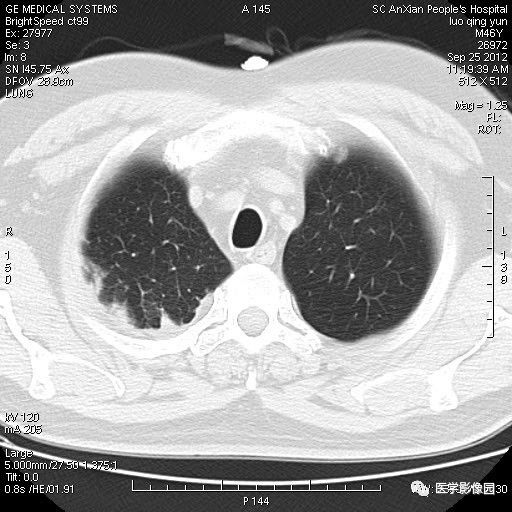

影像学表现:右上肺见不规则团块状高密度阴影,略有分叶级毛刺,边缘模糊,邻近胸膜增厚,增强扫描呈轻中度强化。

诊断结果:右上肺炎性假瘤

本病影像学表现无绝对特征性。单发多见,多位于肺表浅部位,多呈圆形或椭圆形,直径多在2-5cm或更大;多有假包膜,边缘多清晰光整,有时也毛糙,并可有分叶或毛刺;邻近胸膜局限性增厚、牵拉,病灶边缘呈桃尖样突起即桃尖征(尖端指向胸膜);增强扫描多呈中度均匀强化,持续时间较长。亦可显著强化。